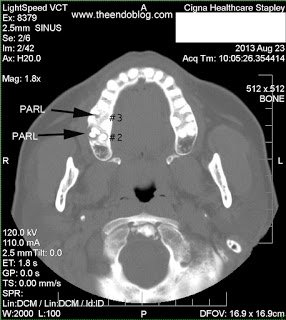

Endodontic diagnosis, including CBCT, determines that tooth #2 has a prior root canal with a root fracture and extraction is recommended. Tooth #3 has a prior RCT with apical abscess – caused by a missed MB#2 canal during the initial root canal treatment. Retreatment of the root canal #3 is recommended.

After 6 months, extraction of tooth #2 and retreatment of tooth #3 has shown periapical healing. The potential odontogenic source of the sinus infection has been eliminated. Since the Mx sinus continues to show opacification, the patient is referred back to Dr. Haegen for continued sinus evaluation and treatment.